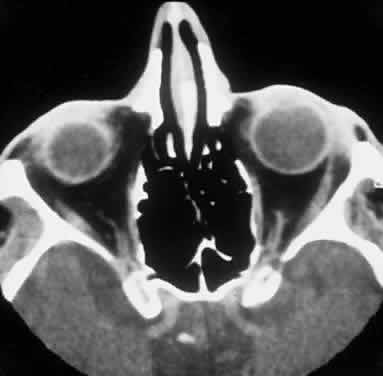

Computed tomography (CT) accurately demonstrates the molding of the mass to orbital structures, such as the globe and orbital bones, without bony erosion except in large cell lymphoma (Fig. 7). CT is used to localize the lesion, which tends to be unilateral and in both the intraconal and extraconal spaces. Lesions limited to the conjunctiva tend to be more benign with a better long-term prognosis, whereas those that extend into the orbit tend to be more malignant. Conjunctival lesions remain localized in 90% of cases, whereas orbital and lid lesions have a higher rate of systemic extranodal involvement.63 Lymphoid lesions of the lacrimal gland appear as a diffuse vertical expansion of the gland, which mold to both the globe and orbital bone without producing a bony fossa or erosion64 (Fig. 8). If the lesion extends beyond the orbital rim, the palpebral lobe of the gland is involved, and posterior or orbital lobe involvement appears as a straight line against orbital fat. Pleomorphic adenoma, on the other hand, appears as an oval, globular lesion with, in 80% of cases, adjacent bone changes caused by the firmer stroma of the tumor. Because epithelial tumors usually arise in the orbital lobe, extension beyond the orbital rim is not a feature.65 CT scan cannot distinguish between inflammatory and lymphoid lesions, because both lesions are homogeneous and enhance with intravenous contrast, and at biopsy, orbital lymphoid lesions are pink with a friable texture caused by the absence of stroma.66–68 The subtype and malignancy of the lesion can only be determined morphologically. The following subtypes of B-cell nonHodgkin's malignant lymphoma—extranodal B-cell marginal zone lymphoma, follicle center cell lymphoma, small lymphocytic lymphoma, lymphoplasmacytoid lymphoma, mantle cell lymphoma, large cell lymphoma, and Burkitt's lymphoma—are discussed in the approximate order of frequency with which they occur in the orbit.

Fig. 7. A CT scan, axial view, of the patient in Figure 6 showing molding of the lymphoma to adjacent extraocular muscle, globe, and medial orbital wall.